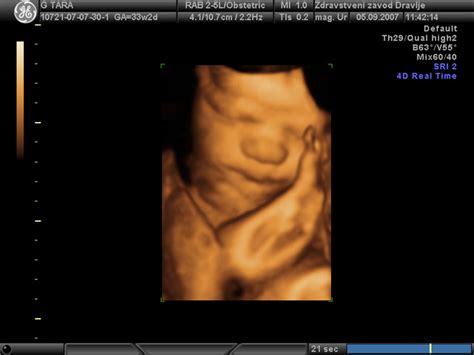

Do približno 35. tedna nosečnosti ima otrok v maternici dovolj prostora, da lahko pogosto menjava svojo lego. Vendar pa se v 36. tednu nosečnosti, zaradi hitre rasti in posledičnega zmanjšanja prostora, otrok običajno umiri in zavzame najudobnejšo lego, v kateri ostane do konca nosečnosti. Najpogosteje si izbere položaj z glavico navzdol, saj se tako najbolje prilega jajčasti obliki maternice. Včasih pa se iz različnih razlogov otrok ustali v medenični vstavi, kar pomeni, da je obrnjen z ritko ali nogicami naprej.